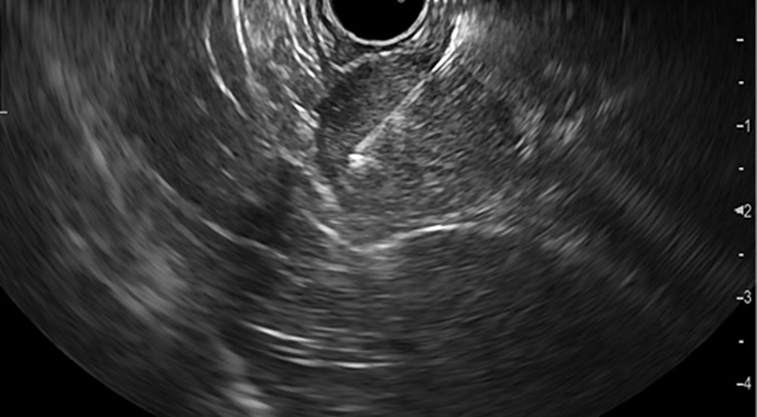

A 37-year-old leucodermic woman with no relevant past history presented with 1-month history of new-onset epigastric pain and bloating. She denied any other symptoms. She underwent an esophagogastroduodenoscopy that revealed a 25-mm subepithelial lesion in the gastric antrum (Fig. 1). Tunnel biopsies were done and were unrevealing. She underwent an endoscopic ultrasound (EUS) that showed a 25-mm hypoechogenic subepithelial lesion originating in the muscularis propria (Fig. 2). EUS-guided fine-needle aspiration (FNA) with a 25-G needle (Boston Scientific®) was performed (2× passes using suction technique), revealing cell nests without atypia, that were focally positive for smooth-muscle actin and synaptophysin, and negative for chromogranin and CD117. KIT and PDGFRA mutations were also negative. Unfortunately, the sample was inadequate for further study. A staging CT was performed excluding distant metastasis. Since investigations thus far were inadequate to exclude a malignant process, she underwent laparoscopic-wedge gastrectomy. Histopathology revealed a solid, epithelioid, and richly vascular tumor without cellular atypia (Fig. 3). Immunohistochemistry was similar to that previously performed and complemented with positive calponin (Fig. 4) and negative cytokeratin AE1/AE3 (Fig. 5), making the diagnosis of a glomus tumor.

Fig. 2: EUS showing a 25-mm hypoechogenic subepithelial gastric lesion originating in the muscularis propria.

Glomus tumors are rare mesenchymal neoplasms that originate in modified smooth-muscle cells (1-3). Despite being highly vascularized, they are most often benign (3). They are frequently found in the skin and subcutaneous tissue, although they can also be located in the gastrointestinal tract, most commonly in the stomach (2, 3). Gastric glomus tumors are usually located in the antrum (2, 3). Clinical symptoms are nonspecific, ranging from dyspepsia to gastrointestinal bleeding (3). Endoscopically, they appear as a smooth submucosal lesion, usually 2-3 cm in size, and present as an ulcerated submucosal lesion in roughly 45% of cases (3). On EUS, they typically originate from the muscularis propria (4th echo layer) but can also be found in the submucosal or mucosal layers (1). Additionally, they can present either as hyperechoic or hypoechoic, usually have internal hyperechoic foci, and present a prominent Doppler signal consistent with the vascular nature of these tumors (1, 2). However, it can be difficult to distinguish them from other subepithelial lesions (e.g., gastrointestinal stromal and neuroendocrine tumors) since they do not exhibit specific distinguishing features on EUS (2). EUS-FNA is an effective method to obtain cytological specimens of gastric submucosal neoplasms, allowing for an adequate histopathological evaluation when using the cell-block technique. However, to ensure an adequate diagnosis of a gastric submucosal lesion, it is important to perform an immunohistochemical study on the cell block (4). Gastric glomus tumors are typically positive for actin, calponin, and vimentin, and negative for CD117, CD20, and CD45, chromogranin A, desmin, and S-100 protein, allowing the distinction of these tumors in the differential diagnosis (3). Since malignant transformation has been described, a complete resection of the lesion is mandatory for definitive treatment (2, 3). The surgical approach depends on the location and size of the tumor. Zhang et al. (2) reported an effective endoscopic approach through endoscopic submucosal dissection technique. However, due to its infrequency, there are insufficient data to establish guidelines regarding management, including the need for postoperative surveillance.